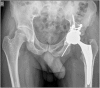

Poor prognosis factors in surgical treatment of acetabular fracture-dislocations have been well established but there is little information about how morphological abnormalities of the hip may affect the surgical outcome. Hip anatomy has a wide range of variations. Morphological abnormalities of the hip can also be observed in patients with acetabular fractures. We present a case of a complication in a patient with a complex acetabular fracture, acetabular retroversion and femoroacetabular impingement. A 31-year old male patient was transferred to our trauma center following a high speed road traffic accident. Trauma series CT revealed cerebral contusion, subdural hematoma, aortic dissection and a left transverse plus posterior wall acetabular fracture. The left hip was reduced and the acetabular fracture was treated with a Kocher Langenbeck approach in prone position. The pelvic X- ray evidenced an anatomic reduction and signs of acetabular retroversion with positive posterior wall sign and crossover sign. CT scan evidenced increased alpha angle in the femoral head neck junction. During the follow up, 2 months after the acetabular fixation, patient suffered a posterior left hip dislocation and a total cementless hip arthroplasty was performed. Patients with acetabular retroversion and femoroacetabular impingement (CAM lesion) may be at risk of posterior dislocation. The influence of acetabular version and impingement may be also closely involved in how challenging the determination of hip stability can be in patients with posterior wall acetabular fractures. Acetabular retroversion and FAI may be related to the dislocation of unstable patterns with small fragments (wall sizes less than 20%). In this case postoperative precautions were not enough. We believe capsular reattachment with anchors and bracing may be useful in these selected cases. As these patients are not candidates for retroPAO (the recommended treatment for acetabular retroversion) maybe arthroscopic anterior wall riming and CAM resection should be performed at an early stage to decrease or avoid fulcrum.